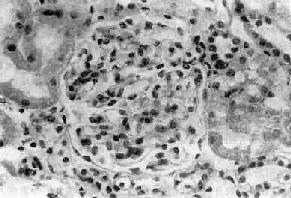

主要病变为肾小球系膜细胞和基质增生,系膜区增宽(图12-10,图12-11)。毛细血管壁无明显变化,管腔通畅。系膜内可有少数单核细胞和中性粒细胞浸润。病变严重者可引起系膜硬化。

图12-10 弥漫性系膜增生性肾小球肾炎

肾小球系膜区略增宽,系膜细胞数量增多